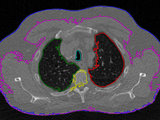

A recursive region growing algorithm for 2D and 3D grayscale image sets with polygon and binary mask output. The main purpose of this function lies on clean and highly documented code.